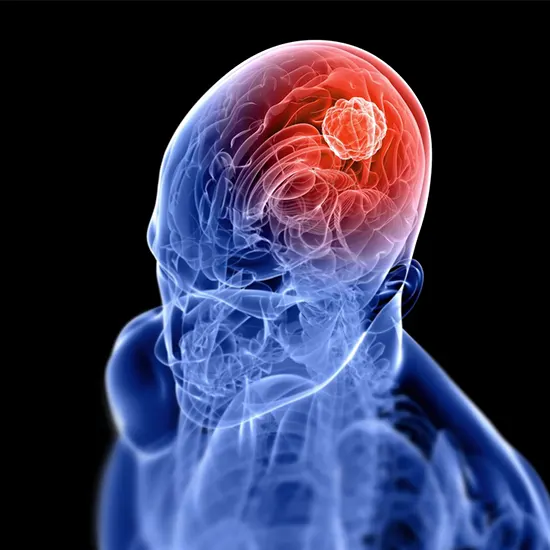

Glioma is a kind of brain tumour that originates in the glial cells, which are the supportive cells that encompass and guard the neurons in the brain. Gliomas can manifest in any section of the brain or spinal cord and can be both benign and malignant.

Glioma is a kind of brain tumour that arises from the glial cells, which are the supportive cells that encompass and guard the neurons in the brain. Glial cells play an essential function in the characteristic and preservation of the brain, and when they emerge as ordinary and begin to divide uncontrollably, they can shape tumours.

- Gliomas occur from the glial cells that encompass and guide the neurons in the brain. These tumours can advance in any section of the brain or spinal wire and can be both benign and malignant.

- The pathophysiology of glioma entails the uncontrolled increase and proliferation of glial cells, which leads to the formation of a mass or tumour.

- The tumour can compress and displace surrounding brain tissue, which can lead to a range of symptoms, relying on the area and dimension of the tumour.